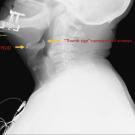

A 74-year-old man with a history of chronic obstructive pulmonary disease presented to the emergency department reporting hoarseness of his voice and difficulty eating 2 days prior to his hospital...